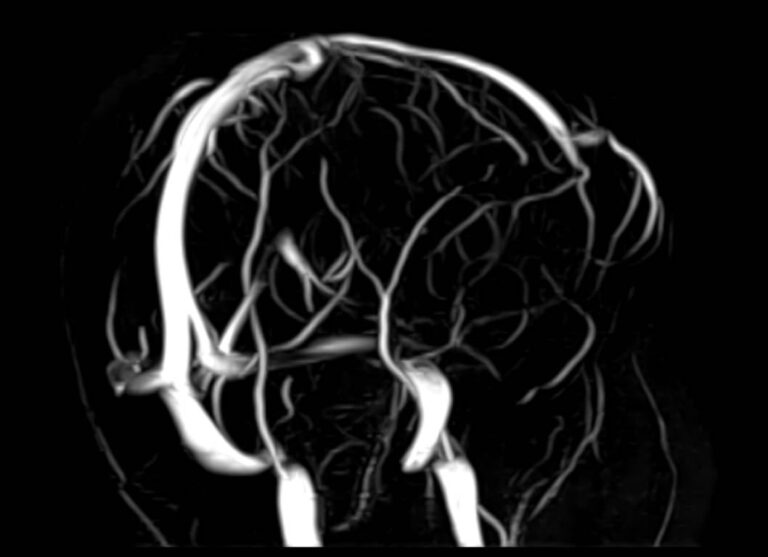

МРТ головного мозга является высокоинформативным методом исследования центральной нервной системы, который дает возможность оценить состояние всех структур головного мозга и поставить правильный диагноз. Стандартную МРТ головного мозга дополняет МР-венография, которая позволяет получить детальную картину строения и функционального состояния венозной системы мозга.

В клинике «Доступная медицина» проводится МРТ головного мозга и МР-венография головного мозга на современном аппарате TOSHIBA VANTAGE TITAN 1,5 Тесла, который обладает высокой чувствительностью и соответствует всем мировым стандартам качества диагностики. Напряженность магнитного поля 1,5 Тесла обеспечивает высокую четкость изображения и позволяет выявлять заболевания на ранних стадиях развития. Процедура МРТ безопасна, так как томограф не испускает рентгеновского излучения, полностью безболезненна и имеет доступную стоимость.

• участки сужения, извитость, образование петель и перегибов сосудов;

• нарушения оттока крови за счет тромбообразования в венозном русле;

• ангиомы, сосудистые мальформации.